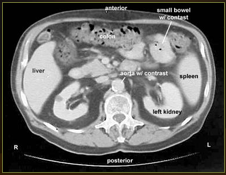

What type of diagnostic test is shown here?

CT abdomen with contrast